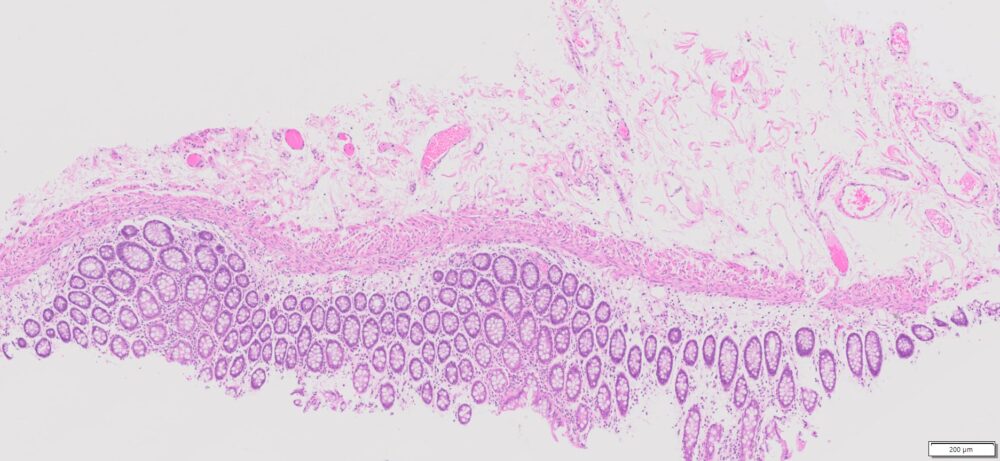

| SKU# | Organ | Pathology Diagnosis | Gender | Age | Grade | TMN | Thickness | IHC Test |

| HuPS-07003A | Human Colon | Normal colon tissue | Female | 50 | — | — | 5 μm | Ki67 |

Human tissue was fixed in formalin immediately after excision and embedded in paraffin. The tissue sections were 5 µm in thickness and mounted each on positively charged glass slides.